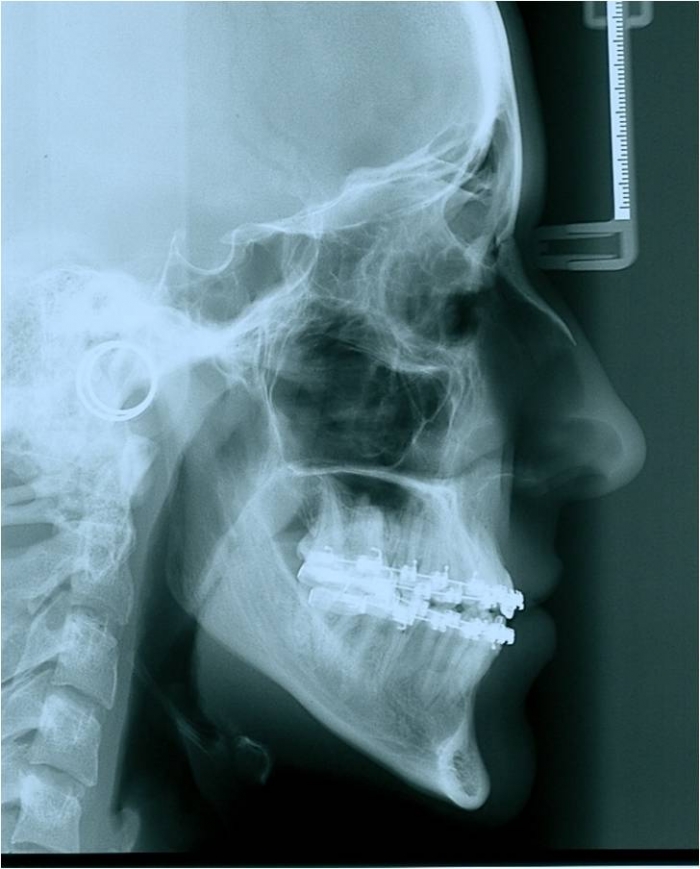

Telerradiografia de perfil inicial - Clínica Cliniface

Telerradiografia de perfil inicial